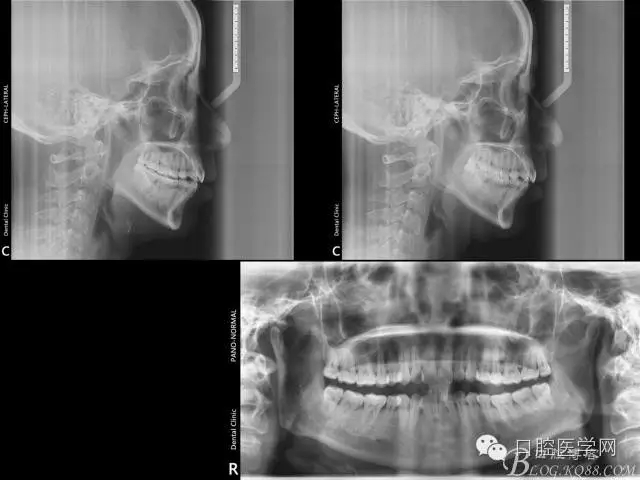

初診照片

2016.3.3初裝矯正器,014Tn絲激活牙齒,利用交互支抗初步排齊前牙,為主弓絲置入創(chuàng)造更好條件。